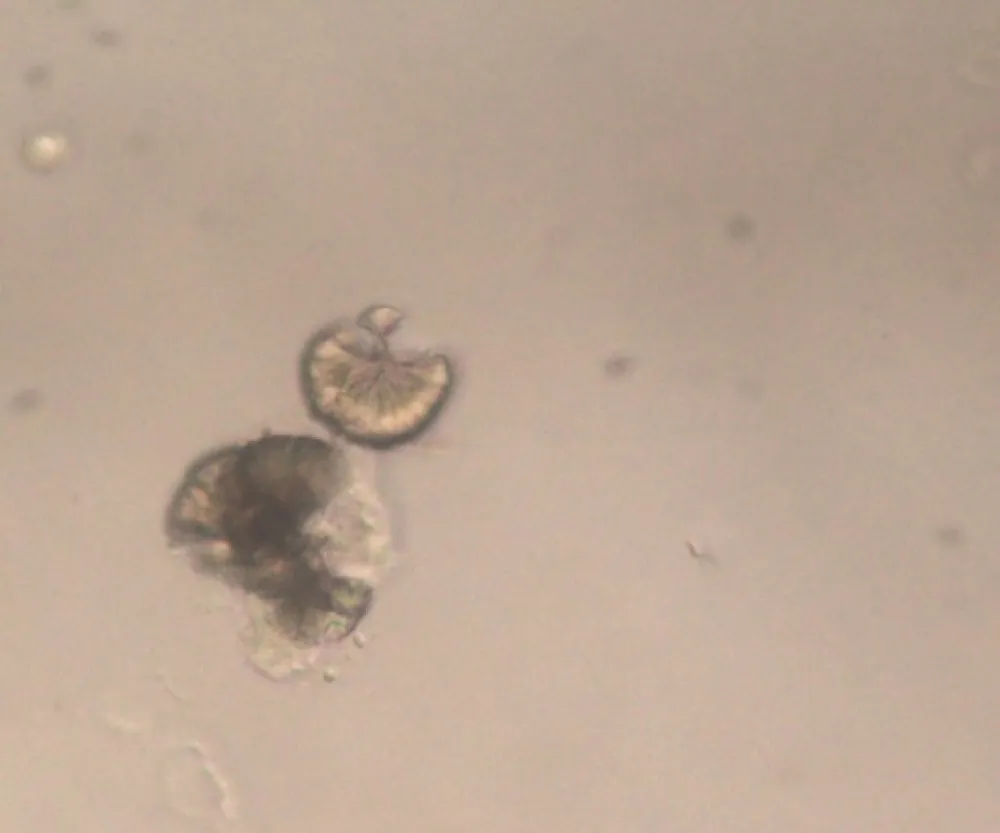

Necrose cortical renal, uma causa subdiagnosticada de IRA

Necrose cortical renal, uma causa subdiagnosticada de IRA

Frequentemente nos deparamos com pacientes que evoluem com quadro de IRA "desproporcional" ao quadro séptico, necrose cortical renal é uma entidade que não pode ser esquecida, principalmente em pacientes com complicações obstétricas